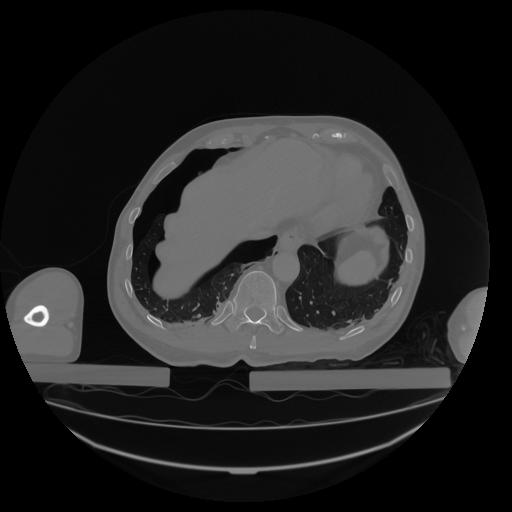

34 CUERPO,CE,Vol,1.0,CUERPO,,